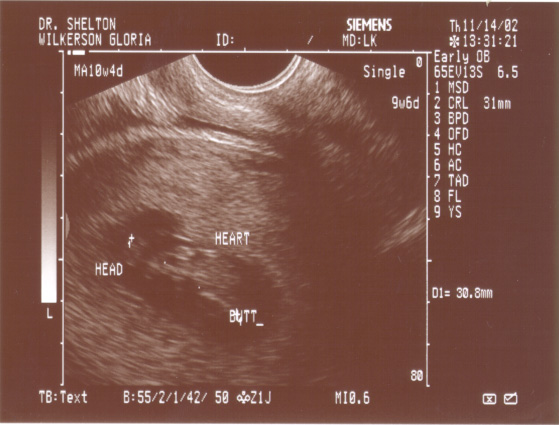

PICTURE 2:

The second picture, just a couple of

minutes later here shows our baby, and

it's swung itself around 180 degrees!